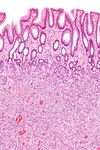

| Hyperplastic | Serrated unbranched crypts | لا | Hyperplastic polyposis syndrome | |

| Sessile serrated adenoma | Similar to hyperplastic with hyperserration, dilated/branched crypt base, prominent mucin cells at crypt base | نعم | ||

| Inflammatory | Raised mucosa/submucosa with inflammation | If dysplasia develops | Inflammatory Bowel Disease, ulcers, infections, mucosal prolapse | |

| Tubular Adenoma (Villous, Tubulovillous) | Tubular glands with elongated nuclei (at least low-grade atypia) | نعم | ||

| Traditional Serrated Adenoma | Serrated crypts, often villous architecture, with cytologic atypia, eosinophilic cells | نعم | ||

| متلازمة پويتز-جيگرز | Smooth muscle bundles between nonneoplastic epithelium, "Christmas tree" appearance | لا | متلازمة پويتز-جيگرز | |

| سليلة الشباب | Cystically dilated glands with expanded lamina propria | Not inherently, may develop dysplasia | Juvenile polyposis syndrome, identical polyps in Cronkhite-Canada syndrome | |

| Hamartomatous Polyp (Cowden Syndrome) | Variable; classical mildly fibrotic polyp with disorganized mucosa and splaying of muscularis mucosae; also inflammatory, juvenile, lipoma, ganglioneuroma, lymphoid | لا | متلازمة كاودن | |

| Inflammatory fibroid polyp | Spindle cells with concentric arrangements of spindle cells around blood vessels and inflammation rich in eosinophils | لا |